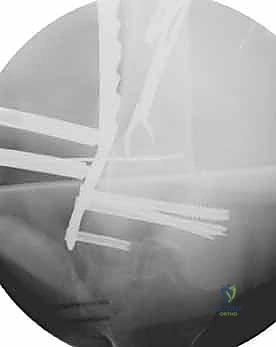

تُعد جراحة "الرد المفتوح والتثبيت الداخلي" (Open Reduction and Internal Fixation - ORIF) هي الإجراء الأكثر شيوعاً ونجاحاً. سنأخذكم في رحلة مفصلة داخل غرفة العمليات لنوضح كيف يقوم البروفيسور هطيف بإعادة بناء العظم بدقة هندسية.

قبل بدء الجراحة، يتم رسم خطة دقيقة. يتم وضع المريض على طاولة العمليات المجهزة بأشعة (C-Arm) لضمان التصوير الفوري أثناء الجراحة.

المرحلة الثالثة: إرجاع العظم (Reduction)

هذه هي الخطوة الأكثر أهمية. يقوم الدكتور هطيف بإعادة القطع العظمية المكسورة إلى مكانها التشريحي الأصلي. إذا كان الكسر ممتداً داخل المفصل، يتم تثبيت السطح المفصلي أولاً باستخدام مسامير دقيقة لضمان سطح أملس يمنع الاحتكاك والخشونة مستقبلاً.

المرحلة الرابعة: التثبيت النهائي بالشرائح والمسامير (Fixation)

يتم استخدام "شرائح الإغلاق التشريحية" (Anatomical Locking Plates) المصنوعة من التيتانيوم عالي الجودة. هذه الشرائح مصممة خصيصاً لتأخذ شكل الجزء السفلي من عظم الفخذ. يتم تمرير الشريحة أسفل العضلات وتثبيتها بمسامير تغلق داخل الشريحة نفسها (Locking Screws)، مما يوفر ثباتاً ميكانيكياً هائلاً، حتى في حالات العظام الهشة.

في بعض الحالات المعقدة جداً، قد يتطلب الأمر استخدام شريحتين (Dual Plating) لضمان عدم تحرك الكسر أثناء فترة التعافي.

بعد التأكد التام من استقرار الكسر وحركة المفصل عن طريق الأشعة داخل غرفة العمليات، يتم إغلاق الجرح بطبقات متعددة باستخدام خيوط تجميلية لتقليل الندبات، ووضع أنبوب تصريف (Drain) لمنع تجمع الدم.